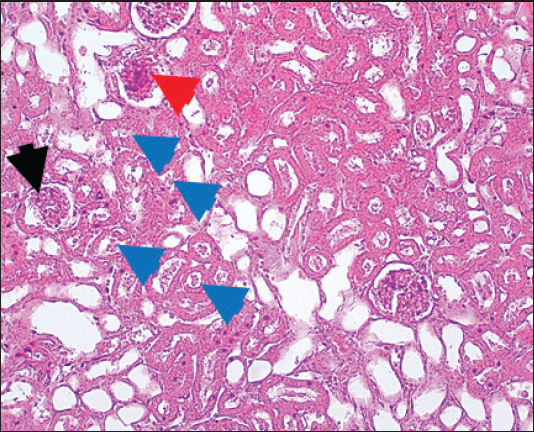

In the control group, histological analysis of kidney sections revealed intact glomeruli and renal tubules (Fig. 1). Conversely, Figure 2 presents a kidney section from the green tea group, which exhibited normal renal tubular epithelial cells, a well-preserved tubular lumen, and an overall normal tubular texture, although some glomeruli showed mild atrophy. The renal section of gentamicin showed atrophy of the glomerular tuft, expansion of the globular space, and significant hyperemia lesions in some glomeruli associated with substantial damage to the superficial cell layer (epithelial cells) in the proximal renal tubules, resulting in a reduction of the tubular lumen space (Fig. 3). In contrast, kidney sections from the gentamicin group that received green tea treatment revealed a marked reveal of both glomeruli and renal tubular epithelium, which appeared normal (Fig. 4 and Fig. 5).

Fig. 3. Kidney of gentamicin group. The section shows clear glomerular tuft atrophy (Black arrow) with increasing of glomerular space and sever hyperemia lesion can be seen in some glomeruli (Red arrow). This section explains severe epithelial cells damage in the proximal renal tubules with decreased the tubular lumen space (Blue arrows). H and E (10X).

It has been shown that gentamicin injected intraperitoneally leads to an increase in creatinine and urea and a decrease in total serum protein in the serum. The increased urea and creatinine levels may suggest renal damage, as evidenced by the data presented (Fig. 3). Studies have found that kidney damage is the primary factor contributing to the rise of urea and creatinine levels in the blood, which can also be influenced by various other factors, including dehydration, dietary intake, and the use of antidiuretic medications (Nwanjo et al., 2005). Additionally, Karunakar et al. (2024) documented an elevation of creatinine and urea levels in groups receiving gentamicin. In addition to the creatinine and urea results, histopathological analysis indicated that gentamicin caused significant renal tissue damage. Consistent with the findings of Vicente et al. (2013), we observed an increase in the urinary excretion of specific proteins in rats treated with gentamicin. Serum-derived proteins are typically excreted in higher quantities in renal diseases that alter the sieving function of the glomerular filtration barrier (Abd-Elrahman et al., 2014). Moreover, an elevation of the MDA levels and a reduction of SOD and GPX levels were observed in the gentamicin-treated rats (Table 4), which was associated with changes in the histological structure of renal tissue. Notably, gentamicin-induced nephrotoxicity was accompanied by a decrease in the activity of oxidative stress biomarkers (GSH-Px, CAT, and SOD) in the renal cortex and an increase in the MDA levels (Sahu et al., 2014).